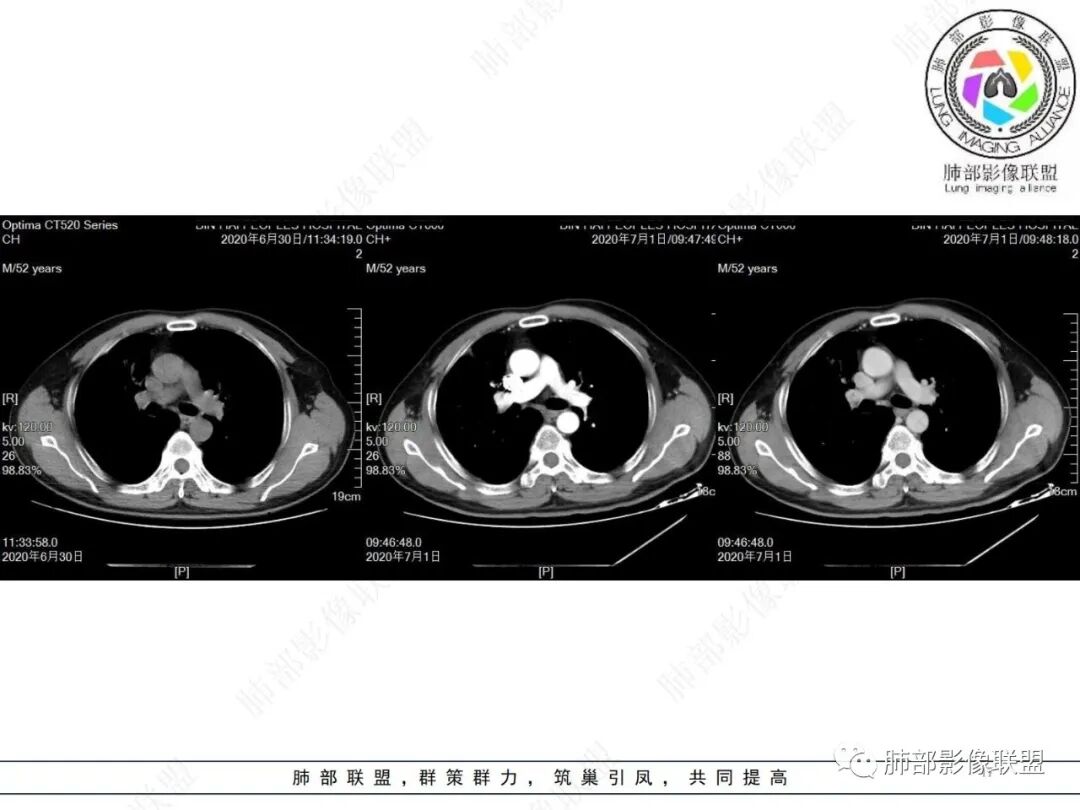

中年男性,有长期吸烟史,右肺上叶不规则肿块,边缘膨隆有分叶,支气管截断,不均匀强化,内有多灶性坏死,癌胚抗原升高,考虑肺癌可能性大,鳞癌可能。鉴别腺癌。

右肺上叶不规则形软组织密度肿块影,边缘见分叶,毛刺,病灶呈宽基底与胸膜相连,病灶内见坏死,增强扫描呈不均匀性强化,右肺上叶支气管截断,纵隔内见肿大淋巴结,肿瘤标志物增高,考虑鳞癌可能,鉴别小细胞癌,腺癌。

老年人,右肺上叶肺不张伴阻塞性炎症,右肺上叶支气管闭塞,增强病灶强化不均匀,可见边缘不清晰的坏死,纵膈淋巴结增大,考虑中央型肺癌,鳞癌可能性大。

右肺上叶不规则肿块,分叶、毛刺,上叶支气管截断,断端圆钝,不均匀强化,其内空泡及坏死,坏死边界不清,考虑腺癌或腺鳞癌,鉴别鳞癌

右肺上叶团块影,边缘膨隆,支气管近端截断,肿块内密度不均匀,见片状坏死,边界不清,纵隔肿大淋巴结,CEA明显增高,考虑恶性,鳞癌?腺鳞癌?

中年男性,长期吸烟,CT示右肺上叶肿块影,有分叶,毛刺,胸膜牵拉,支气管截断,边缘斑片影,病变内有坏死,强化,淋巴结肿大,首先考虑鳞癌可能性大,鉴别腺鳞癌

右上叶支气管截断呈斜坡状,不均匀强化,低密度区实质区边界不清,老年男性,长期吸烟史,考虑恶性,鳞癌首选

不符合鳞癌有四点:1,截断的支气管不在肿块中央,而是外朝内爬行(肿块外缘大于近端)2、支气管截断在前段,前段远端没有阻塞性改变。3、鳞癌是近端强化,远端为阻塞性的不强化粘液栓或明显强化的不张肺组织,这个是中间坏死,周围强化的肿瘤组织。4、肿瘤标志物CEA增高太明显,鳞癌标志物不高。